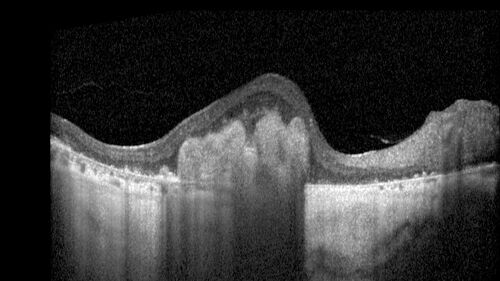

78 year old female with vision loss for 1 week and old macular scar. Images show BRAO with plaques and FA shows occlusion.

BRAO_126199_071725_06.jpg

BRAO and macular scar - plaques in vessel and video